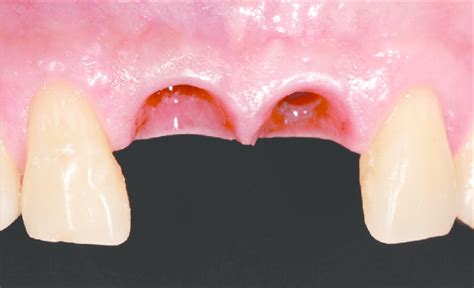

Paciente masculino de 42 años que se presentó en el Departamento de Periodoncia de la Escuela de Graduados de Odontología de la Universidad Católica Santo Domingo. En su primera cita se llenaron las fichas de antecedentes médicos y odontológicos. El paciente presentaba un buen estado de salud general. En la exploración intraoral se puede apreciar ausencia de las coronas de los dientes 8 y 9 (central derecho e izquierdo superior) y caries radicular.

El paciente manifestó que hacía mucho había sufrido un trauma en los dientes 8 y 9, que le habían realizado 2 endodoncias, que luego con el tiempo las coronas cambiaron de color y finalmente se le fracturaron (fig. 1). Se evaluó la condición local y general de los tejidos blandos y duros para la posible colocación de implantes dentales inmediatos como reemplazo de los dientes 8 y 9. También se realizaron coronas provisionales de acrílico para la fase de diagnóstico. En la radiografía periapical se observan los restos radiculares con tratamientos endodónticos previos y lesiones periapicales.

Figura 1. Foto preoperatoria.